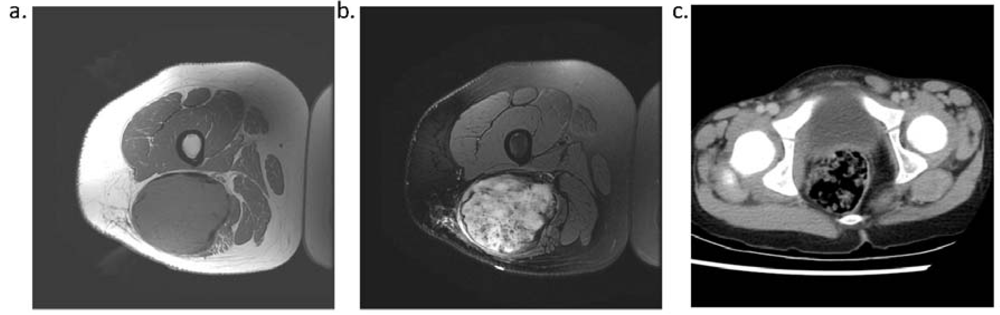

4. Imaging